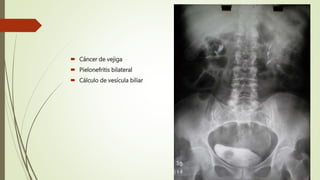

 Cáncer de vejiga

 Pielonefritis bilateral

 Cálculo de vesícula biliar

 Cáncer devejiga  Pielonefritis bilateral  Cálculo de vesícula biliar